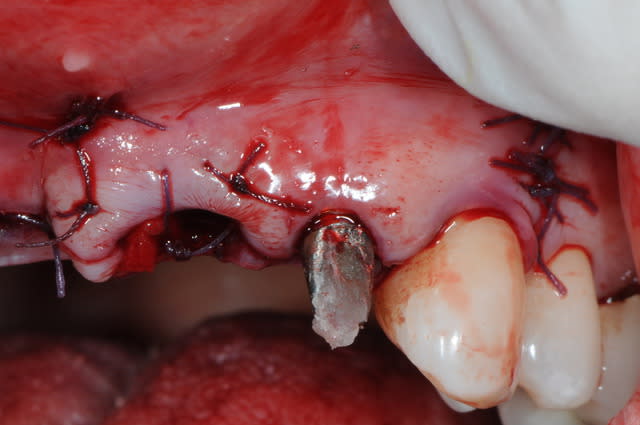

extraction de 12 et 22 pour commencer et pour connaitre la limite maxi d'implantation dans la crête osseuse.

grosse déception quant à la table externe au niveau de 11

pour les axes, j'avoue que je me suis fait avoir comme une bleusaille (mais bon, j'en suis une), je me suis un peu laisser embarquer par l'axe des alvéoles. c'est dure l'implanto.